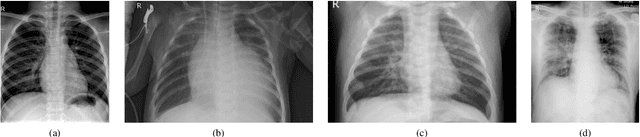

Abstract:Over the last year, the severe acute respiratory syndrome coronavirus-2 (SARS-CoV-2) and its variants have highlighted the importance of screening tools with high diagnostic accuracy for new illnesses such as COVID-19. To that regard, deep learning approaches have proven as effective solutions for pneumonia classification, especially when considering chest-x-rays images. However, this lung infection can also be caused by other viral, bacterial or fungi pathogens. Consequently, efforts are being poured toward distinguishing the infection source to help clinicians to diagnose the correct disease origin. Following this tendency, this study further explores the effectiveness of established neural network architectures on the pneumonia classification task through the transfer learning paradigm. To present a comprehensive comparison, 12 well-known ImageNet pre-trained models were fine-tuned and used to discriminate among chest-x-rays of healthy people, and those showing pneumonia symptoms derived from either a viral (i.e., generic or SARS-CoV-2) or bacterial source. Furthermore, since a common public collection distinguishing between such categories is currently not available, two distinct datasets of chest-x-rays images, describing the aforementioned sources, were combined and employed to evaluate the various architectures. The experiments were performed using a total of 6330 images split between train, validation and test sets. For all models, common classification metrics were computed (e.g., precision, f1-score) and most architectures obtained significant performances, reaching, among the others, up to 84.46% average f1-score when discriminating the 4 identified classes. Moreover, confusion matrices and activation maps computed via the Grad-CAM algorithm were also reported to present an informed discussion on the networks classifications.